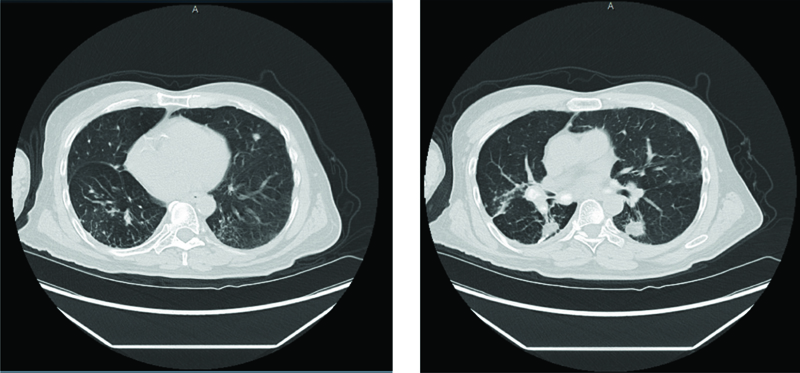

A 69-year-old man with a past medical history of intellectual disability due to prematurity at birth leading to blindness and deafness, asthma, tracheomalacia, seizure disorder, and GERD presented to the emergency room with shortness of breath associated with fever and coughing. This patient has a complex medical history, including multiple prior hospitalizations for recurrent aspiration pneumonia, swallowing dysfunction, and a lung mass. He had a percutaneous endoscopic gastrostomy tube placed seven years ago and does not have oral intake. His vital signs included 85% oxygen saturation on room air, tachycardic with a heart rate 120s beats per minute, and a temperature of 99.5°F. Laboratory results included leukocytosis, anemia, and thrombocytopenia. The patient appeared to be in respiratory distress and was started on high flow nasal cannula 20 liters per minute with a FiO2 of 60%. Computed tomography (CT) of the chest showed mixed perihilar and bilateral pulmonary densities (Figure 1). His previous CT chest from six years ago showed multiple tiny micronodules clustered and scattered throughout both lower lung fields that may be sequelae of granulomatous disease (Figure 2). The patient had a wedge resection lung biopsy twenty years ago that showed presence of lentil starch material in the bronchioles and multifocal foreign body giant cell reaction, subpleural calcified hyalinized nodules, and subpleural fibrosis, consistent with lentil aspiration pneumonia (Figures 3 and 4).

Figure 2

Figures 2A and B. CT chest showed multiple tiny micronodules clustered and scattered throughout both lower lung fields with multiple calcified mediastinal and hilar lymph nodes.